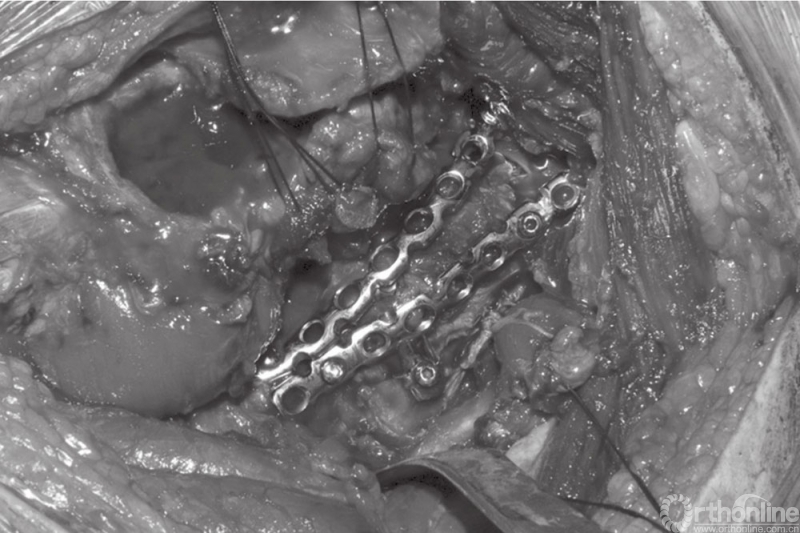

A和B髋臼后壁骨折的固定

预弯钢板需要一定的技巧。对于髋臼壁骨折,钢板需向下弯曲,而上方需进行适当的扭转,以使其更好地贴附于髋臼的后缘和上缘(图24.12)。下方的螺钉通常自髋臼下沟拧入坐骨,不必拧紧。此时,轻轻移动重建钢板,以在最理想的位置进行固定,同时可为弹力钢板提供更好的支撑(图24.13A和B)。随后,拧入上方的螺钉。一般情况下,重建钢板上下各拧入3枚螺钉即可,但是我们依然喜欢选择8~10孔的骨盆重建钢板。

利用重建钢板固定髋臼后柱骨折块

偶尔在后壁骨折线较长或后壁合并后柱骨折时,我们需要第二块重建钢板以加强固定(图24.14)。需要强调的是,术中应避免螺钉穿透至髋关节。在侧位时,可通过控制螺钉拧入的方向远离髋臼以防止螺钉穿透髋关节。在拧入螺钉后,应全方位活动髋关节,以确保关节活动无任何阻碍、螺钉没有拧入关节内。术中多个角度的影像学检查也有助于排查螺钉有无拧入关节内。术中及术后应进行彻底的冲洗。

通过坐骨切迹触摸骨折块表面有助于确认后柱骨折是否完全复位,将带角度的骨盆复位钳夹在坐骨结节上,有助于维持后柱骨折块的前面部分。如果骨折线的角度允许,一个加压螺钉联合中和钢板将有助于骨折的复位与固定。骨折复位后,将一个3.5mm的骨盆重建钢板预弯后放置在后柱的边缘进行初始固定。为了实现对后柱骨折进行良好的加压固定,在多数情况下需要放置第二块钢板。